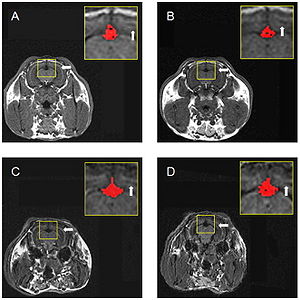

Publication: J Neurosurg. 2016 Jan 1:1-8. PMID: 26722859 Authors: Song F, Hou Y, Sun G, Chen X, Xu B, Huang JH, Zhang J. Institution: Department of Neurosurgery, People's Liberation Army General Hospital, Beijing, China. Background/Purpose: OBJECTIVE Preoperative determination of the facial nerve (FN) course is essential to preserving its function. Neither regular preoperative imaging examination nor intraoperative electrophysiological monitoring is able to determine the exact position of the FN. The diffusion tensor imaging-based fiber tracking (DTI-FT) technique has been widely used for the preoperative noninvasive visualization of the neural fasciculus in the white matter of brain. However, further studies are required to establish its role in the preoperative visualization of the FN in acoustic neuroma surgery. The object of this study is to evaluate the feasibility of using DTI-FT to visualize the FN. Methods Data from 15 patients with acoustic neuromas were collected using 3-T MRI. The visualized FN course and its position relative to the tumors were determined using DTI-FT with 3D Slicer software. The preoperative visualization results of FN tracking were verified using microscopic observation and electrophysiological monitoring during microsurgery. Results Preoperative visualization of the FN using DTI-FT was observed in 93.3% of the patients. However, in 92.9% of the patients, the FN visualization results were consistent with the actual surgery. CONCLUSIONS DTI-FT, in combination with intraoperative FN electrophysiological monitoring, demonstrated improved FN preservation in patients with acoustic neuroma. FN visualization mainly included the facial-vestibular nerve complex of the FN and vestibular nerve. |